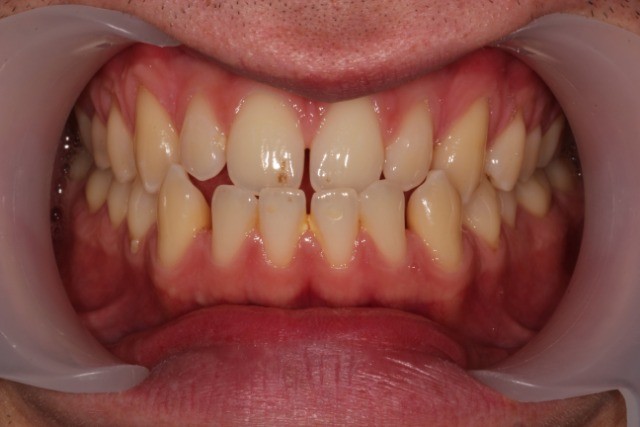

Classe III, articulé croisé antérieur, béance, espacement, diastème

État initial